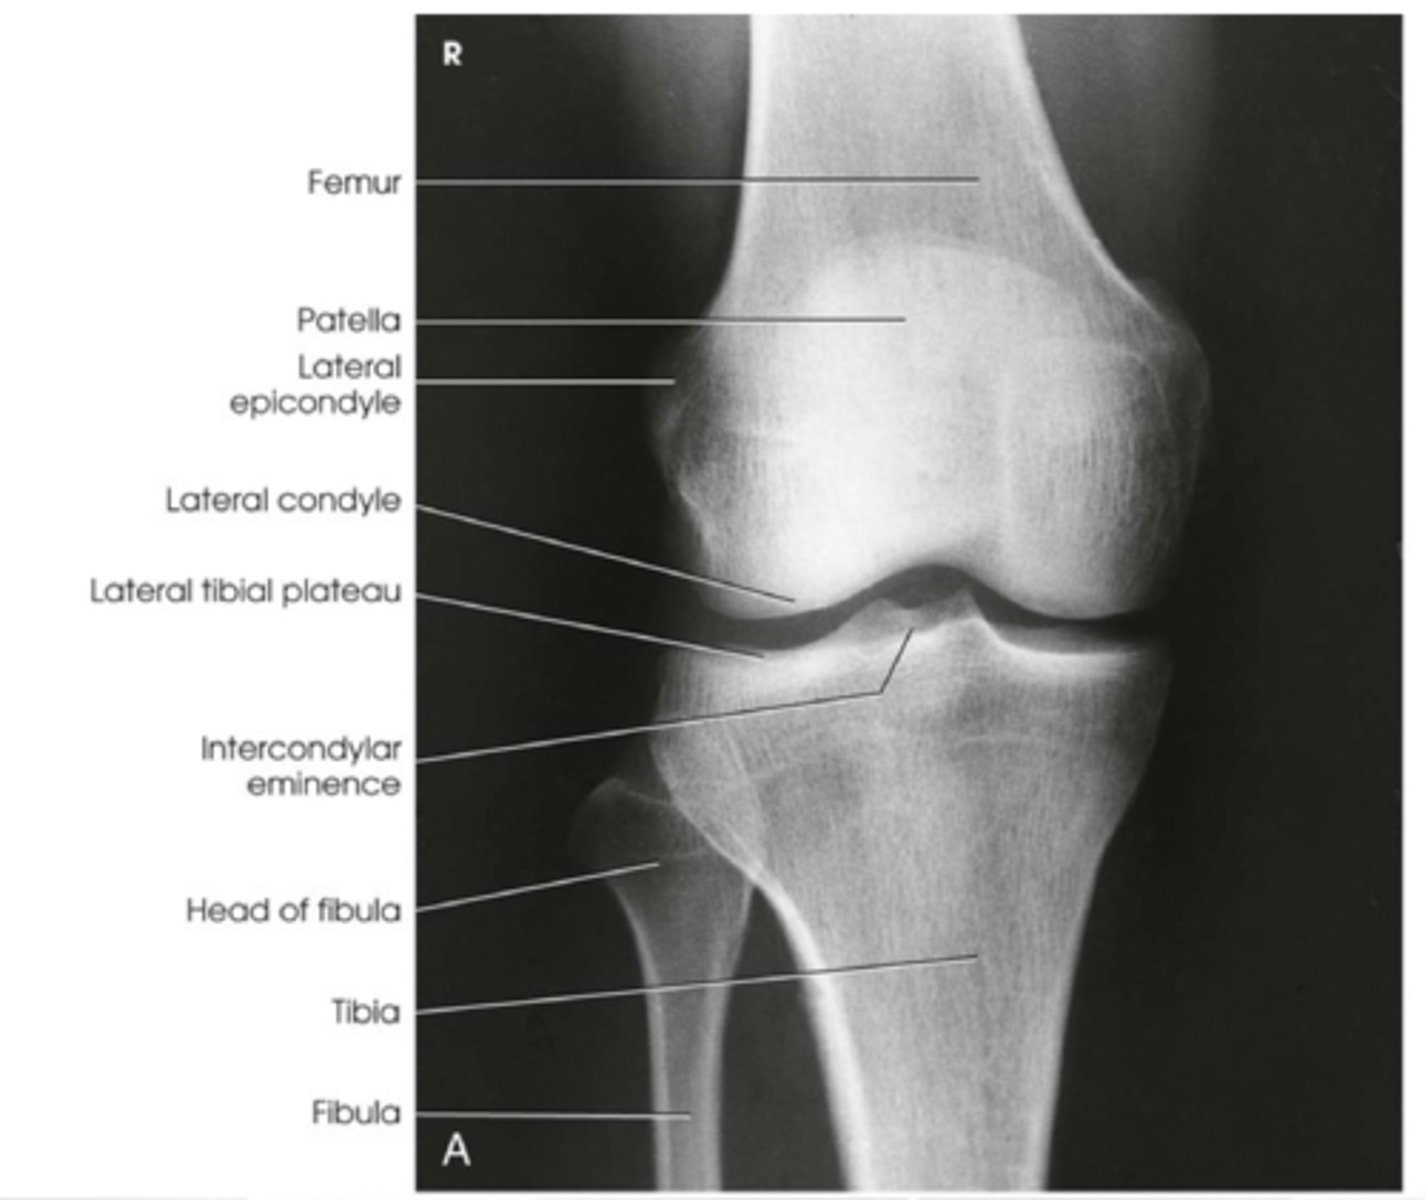

How should we COLLIMATE when doing an AP KNEE projection? What structures should be included in the image?

- to include: the knee joint, distal third of the femur, proximal third of the tibia and fibula and lateral soft tissue borders.

ALSO:

▪ Head of the fibula should be partially obscured by the tibia

▪ Shafts of the tibia and fibula should be separated

▪ Joint space should be clear

▪ Patella centralised